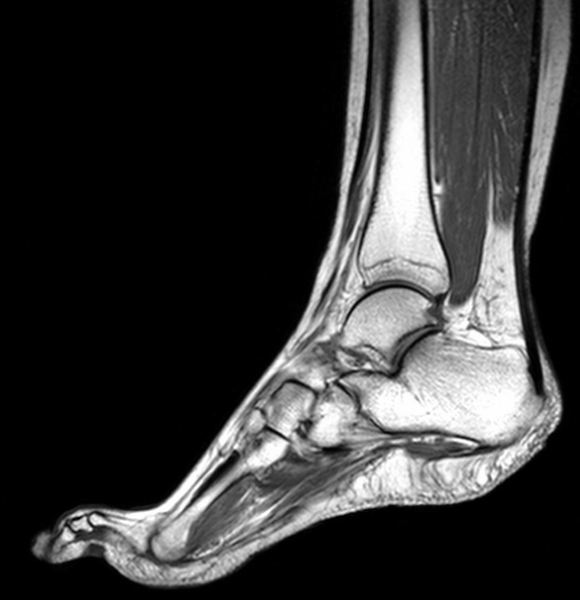

МРТ голеностопного сустава в клиниках Санкт-Петербурга проводят на моделях аппарата томографии с различной мощностью, и это во многом определяет цену обследования. Самый недорогой способ сделать МРТ - записаться на исследование на открытом томографе. Существенно дороже будет стоить сканирование стопы и голени на высокопольном аппарате мощностью 1,5 и 3 Тесла. МР томография голеностопного сустава - это исследование связок, суставных тканей и костей голеностопа, которое назначают врачи, чтобы как можно скорее выявить причину заболевания в этой части ноги и начать лечение. Голеностопный сустав - это важное сочленение в опорно-двигательном аппарате, и если оно выходит из строя, это доставляет человеку массу сложностей, так как теряется возможность нормально ходить.

МРТ голеностопного сустава предоставляет врачам возможность провести дифференциальную диагностику следующих патологий:

• растяжение связок лодыжки;

• тендинит ахиллова сухожилия;

• теносиновит;

• пяточная шпора;

• переломы малоберцовой кости и большеберцовой кости;

• тендиноз задней большеберцовой мышцы;

• ущемление медиального и латерального подошвенных нервов;

• невропатическая артропатия;

• разрывы ахиллова сухожилия;

• болезнь Шарко-Мари-Тута.

Данные магнитно-резонансной томографии могут потребоваться при подготовке к хирургическому вмешательству или в послеоперационный период для контроля результатов лечения и скорости восстановления тканей.